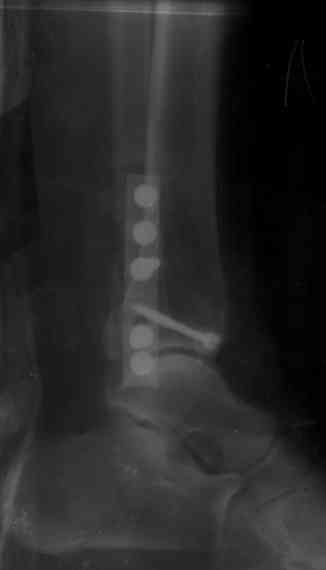

После проведенной дискуссии пришел к выводу, что трансартикулярная диафиксация не совсем приемлима с учетом современных методик остеосинтеза. Кроме того, вычитал, что хрящ разрушается на расстоянии до 0,5 см от места проведения спицы.

Пока я был в интернатуре, предпочитали осуществлять стабильный остеосинтез с ранней функцией. См. приложения и полнотекстный вариант

статьи.